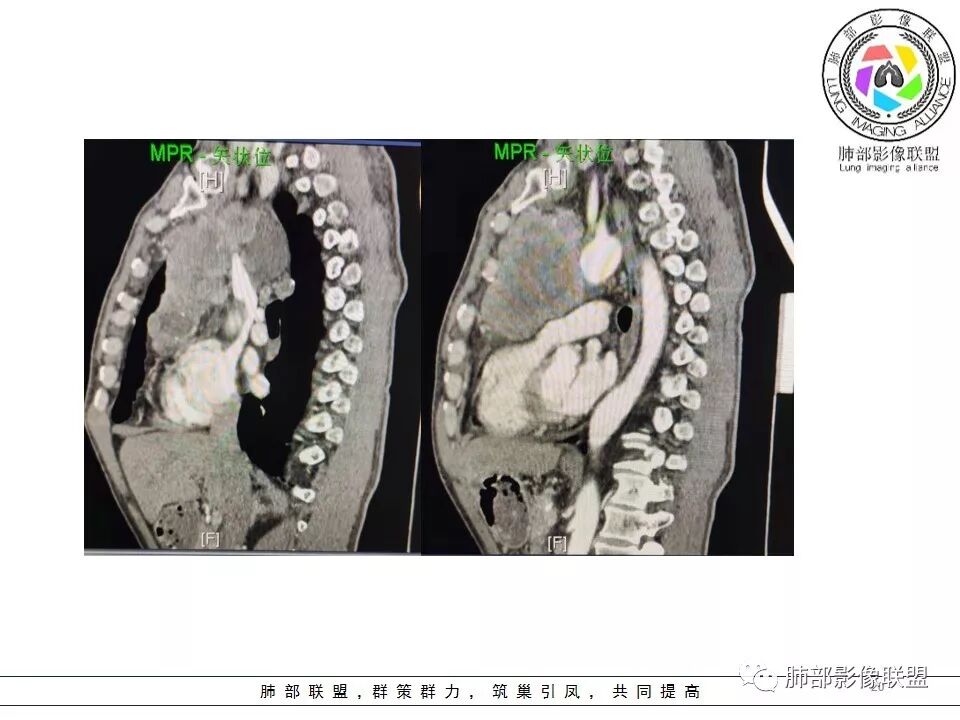

定位没问题:前纵隔。

较大,内有囊变、钙化。

南边:边界大部分清楚,有些地方毛糙。

附近有淋巴结

上腔静脉如何?

心包如何?

大肿块,边缘不清,伴随肿大淋巴结,上腔静脉受侵犯——恶性

侵袭性胸腺瘤?胸腺癌?老年,钙化、肿大淋巴结,边缘侵犯、累及心包、侵犯上腔静脉——支持